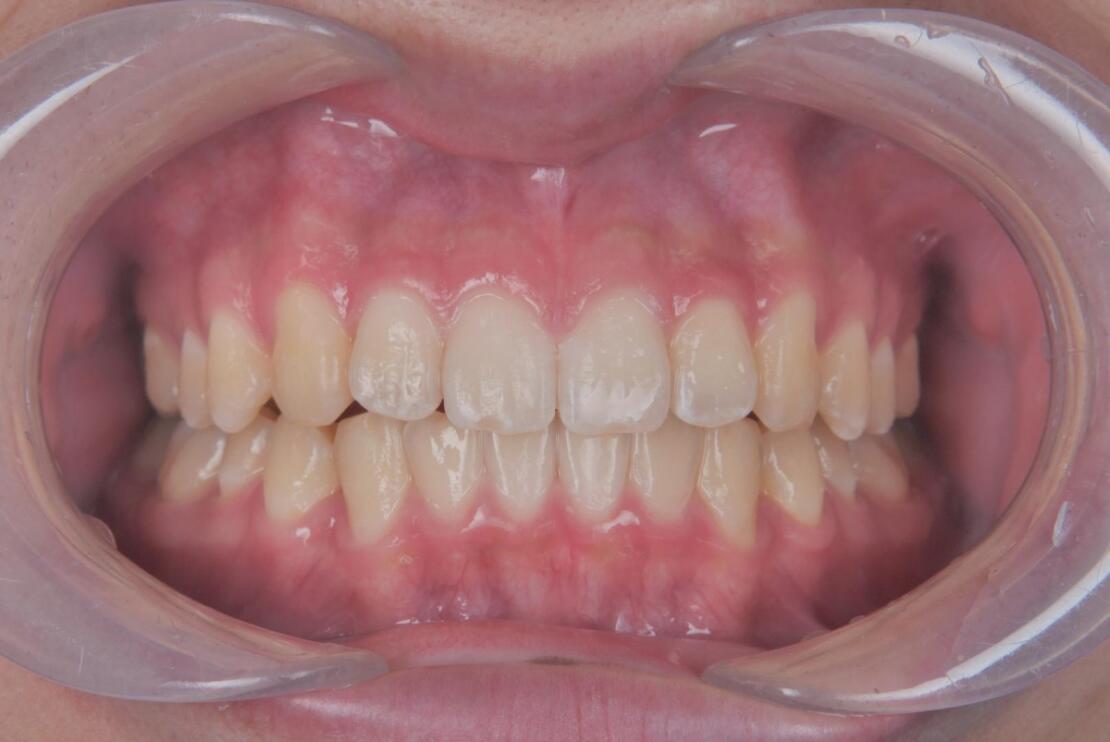

治療期間は1年半で、すき間が改善され、口元の印象が大きく変化しています。

学校生活への影響を最小限に抑えながら、無理なく治療を進めることができた症例で、ご本人だけでなくご家族にもご満足いただく結果となりました。

BEFORE

AFTER